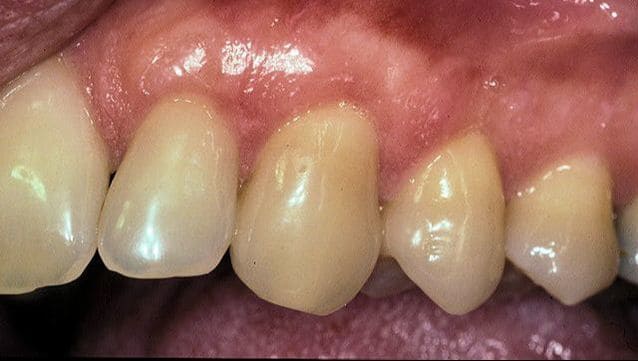

Before

Patient: Jill